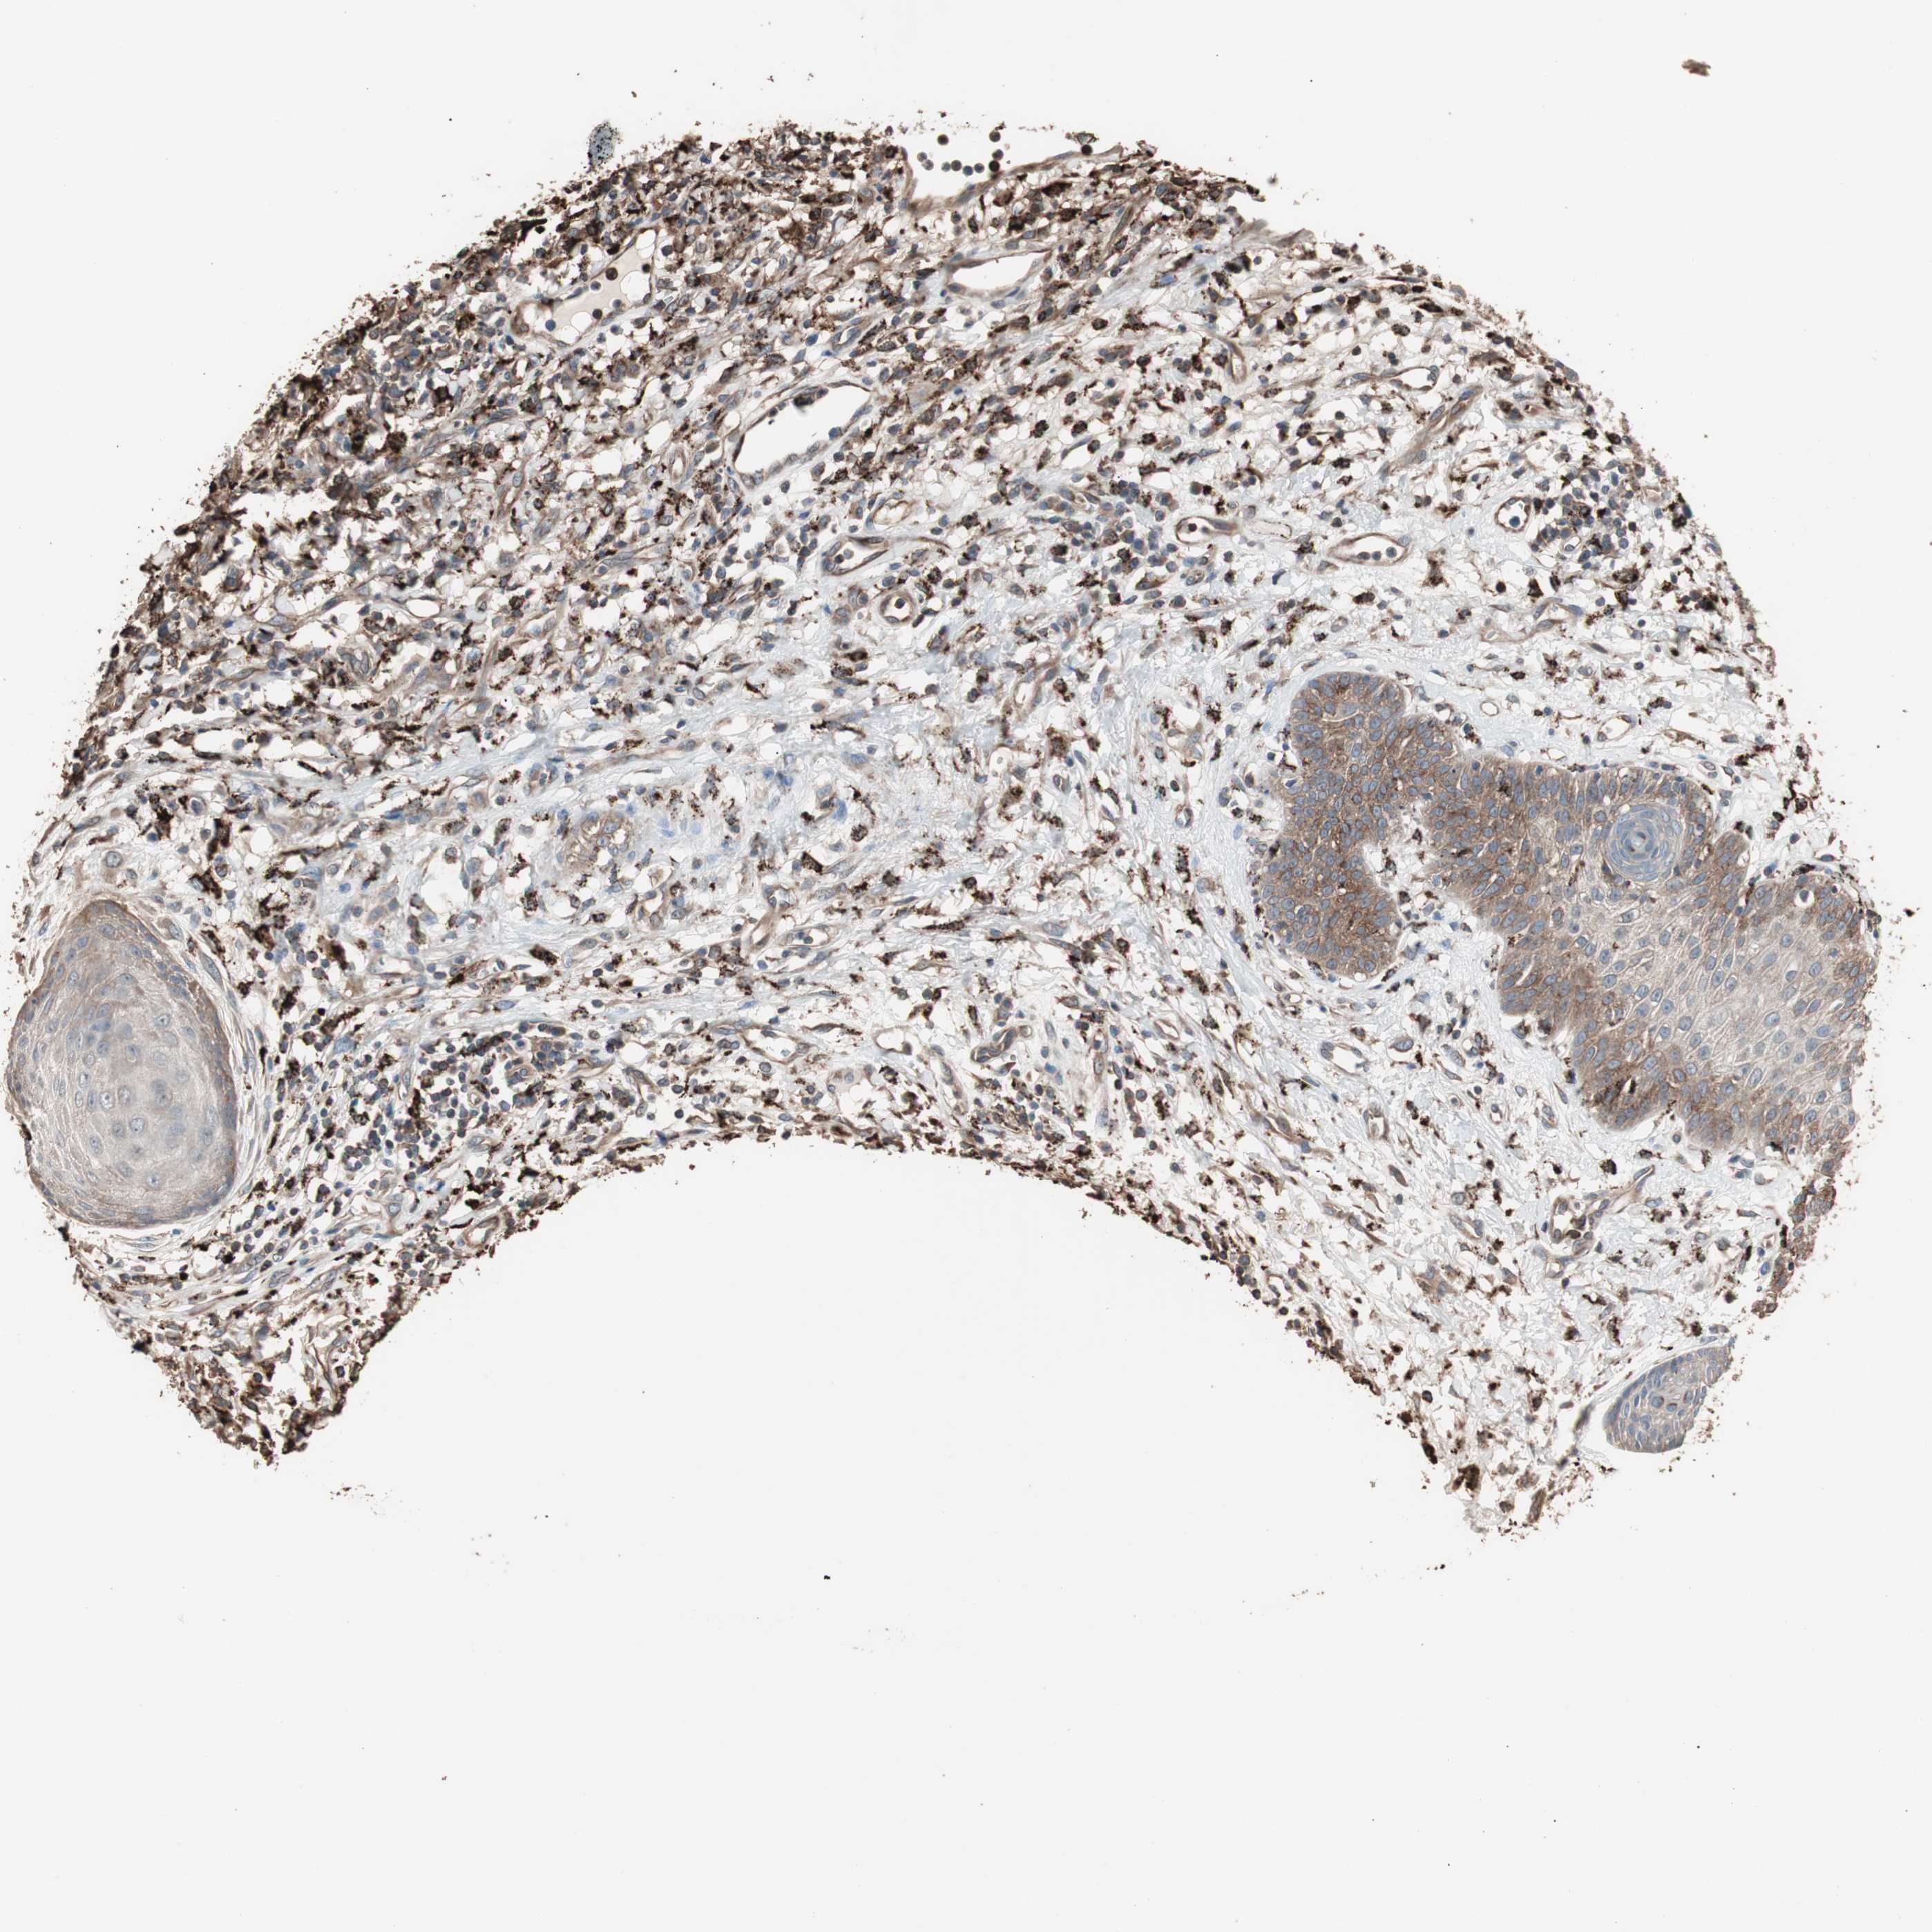

SKIN CANCER - Protein expressioni

A mouse-over function shows sample information and annotation data. Click on an image to view it in a full screen mode. Samples can be filtered based on level of antibody staining by selecting one or several of the following categories: high, medium, low and not detected. The assay and annotation is described here.

Antibody stainingi

Antibody staining in the annotated cell types in the current human tissue is reported as not detected, low, medium, or high, based on conventional immunohistochemistry profiling in selected tissues. This score is based on the combination of the staining intensity and fraction of stained cells.

Each image is clickable and will lead to virtual microscopy that enables deeper exploration of all samples and also displays staining intensity scores, fraction scores and subcellular localization as well as patient and tissue information for each sample.

Antibody HPA006543

Staining

High

Intensity

Strong

Quantity

>75%

Location

Nuclear

Squamous cell carcinoma, metastatic, NOS